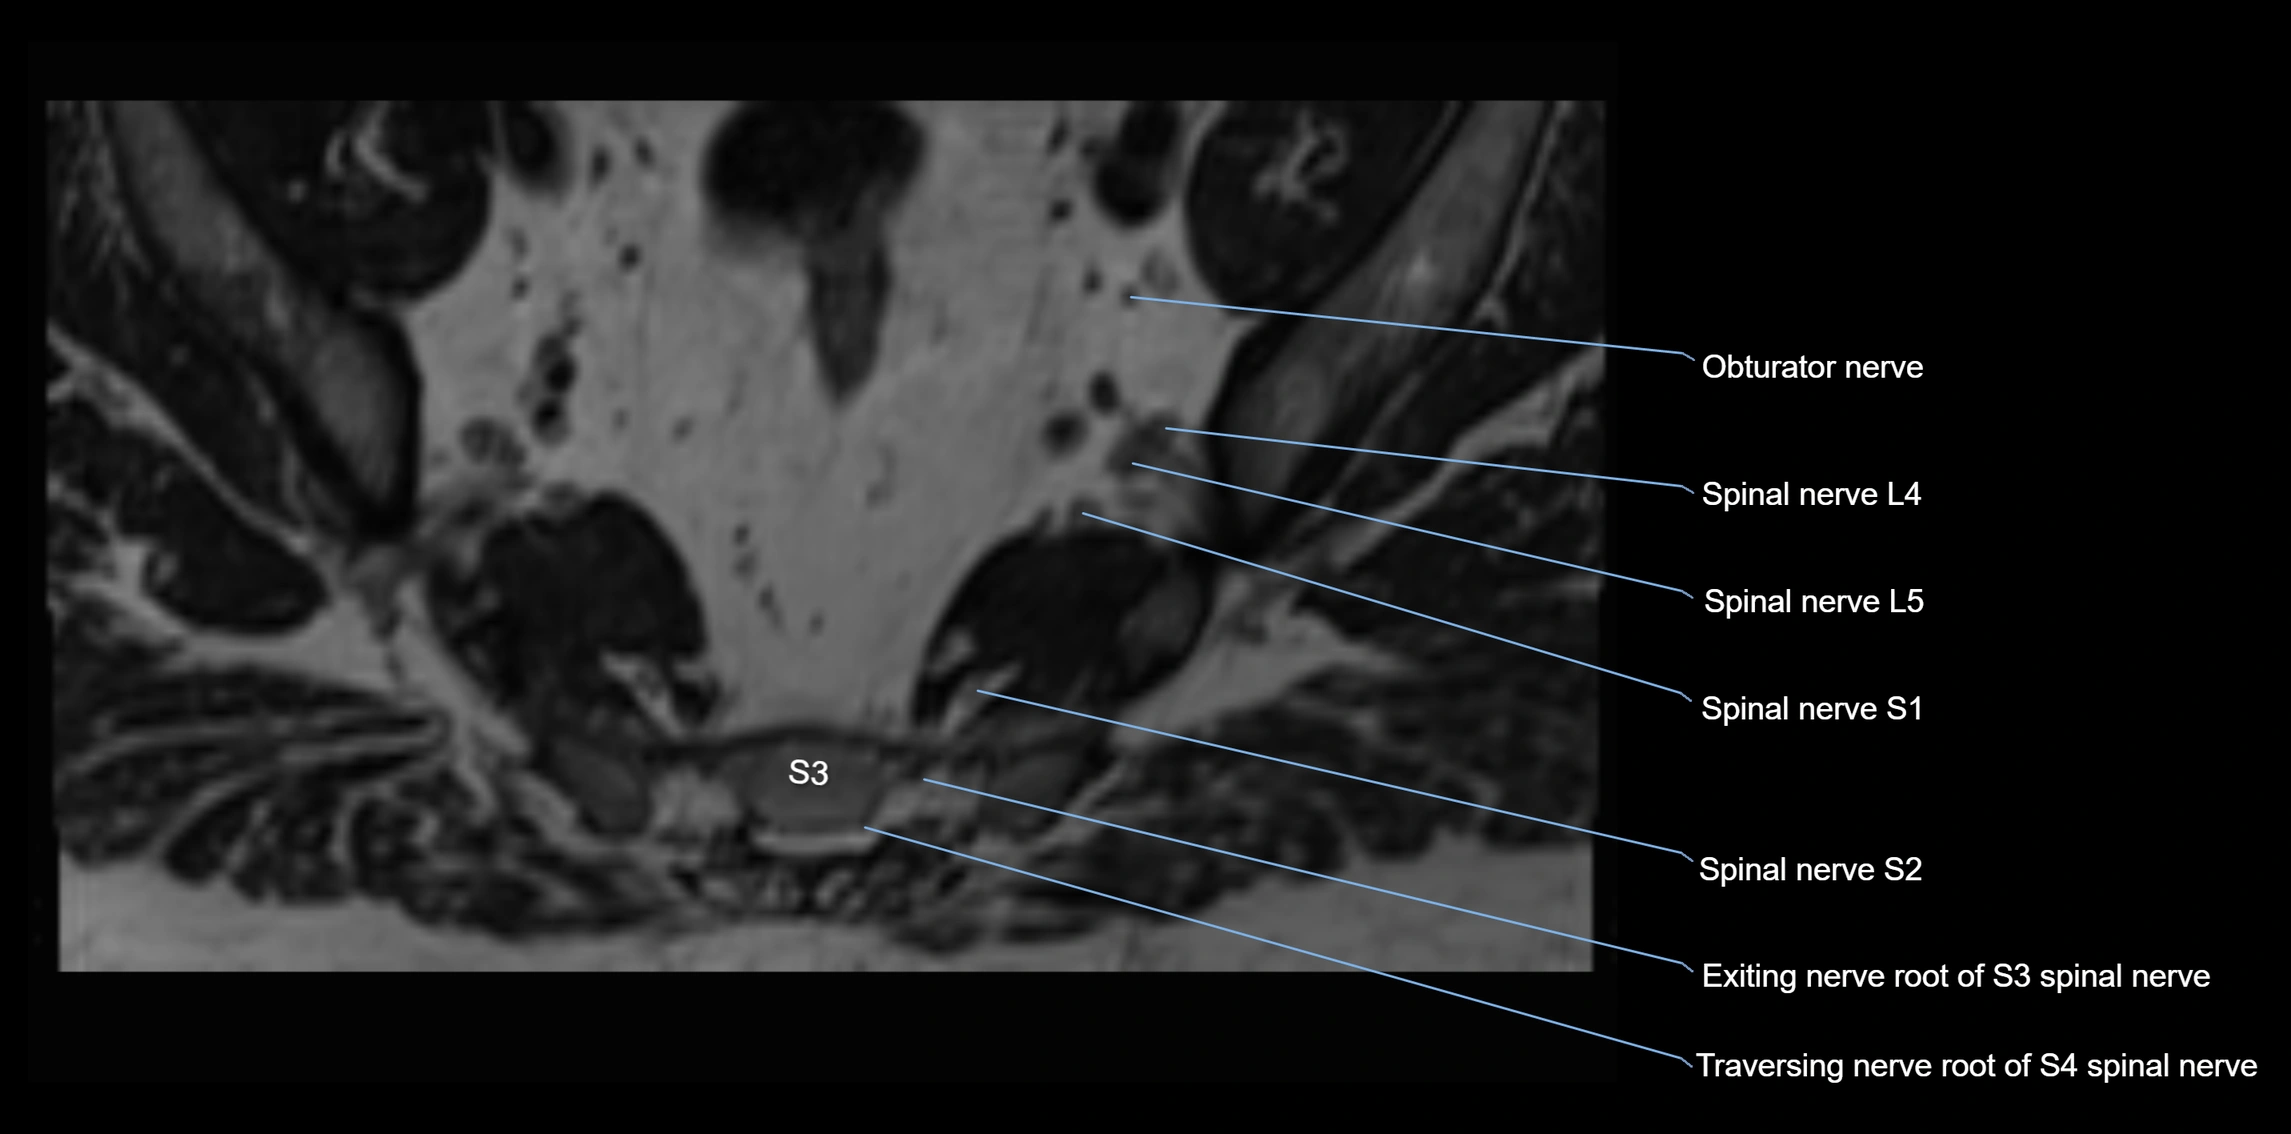

MRI Appearance

T1-weighted images:

• Nerve appears as a very thin low-to-intermediate signal intensity structure

• Surrounded by bright fat, aiding visualization

T2-weighted images:

• Nerve shows intermediate to mildly hyperintense signal compared to muscle

• Pathological involvement appears brighter

STIR (Short Tau Inversion Recovery):

• Normal nerve appears dark

• Inflamed or entrapped nerve appears bright hyperintense

3D T2 SPACE / CISS:

• Nerve appears intermediate to mildly hyperintense compared to muscle

• Surrounded by bright fat or CSF, improving visualization

• Best sequence for mapping small pelvic nerves such as the anococcygeal